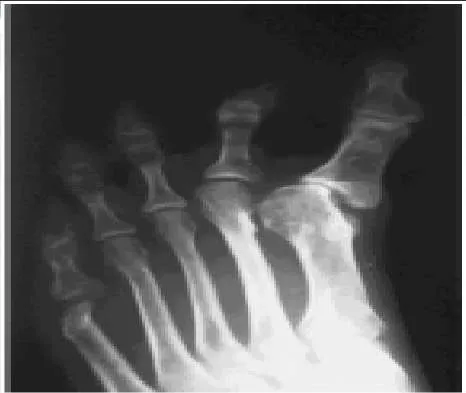

Question 37:

A 29-year-old woman presents for treatment of a swollen foot. Although her foot is not painful, it has been swollen for 2 weeks. The patient walks into the office without any assistive device. On examination, the foot is swollen and warm. The patient does not have protective sensation in the foot, and she denies a history of diabetes and does not have a clinically relevant medical history. A radiograph of her foot is presented (Slide). Which of the following tests will be most helpful in determining the etiology of her condition:

Correct Answer: Hemoglobin A1

Explanation:

This patient most likely has diabetes. Patients may present for the first time with an acute neuroarthropathy of the foot as a result of diabetes, even without a clinical history of the disease. Although the sedimentation rate will likely be elevated, it will not help in the diagnosis. Infection is not a likely consideration in this patient.